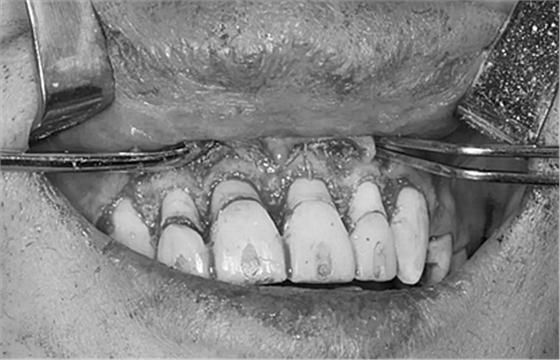

第二次治療是半個月后,這次做了根管充填后將覆蓋在我們身體上的一部分牙齦切除,讓我們埋于牙齦下的身體暴露了一部分,也就是醫(yī)生說的冠延長術。這是為了讓我們變得美觀一些。

冠延長術